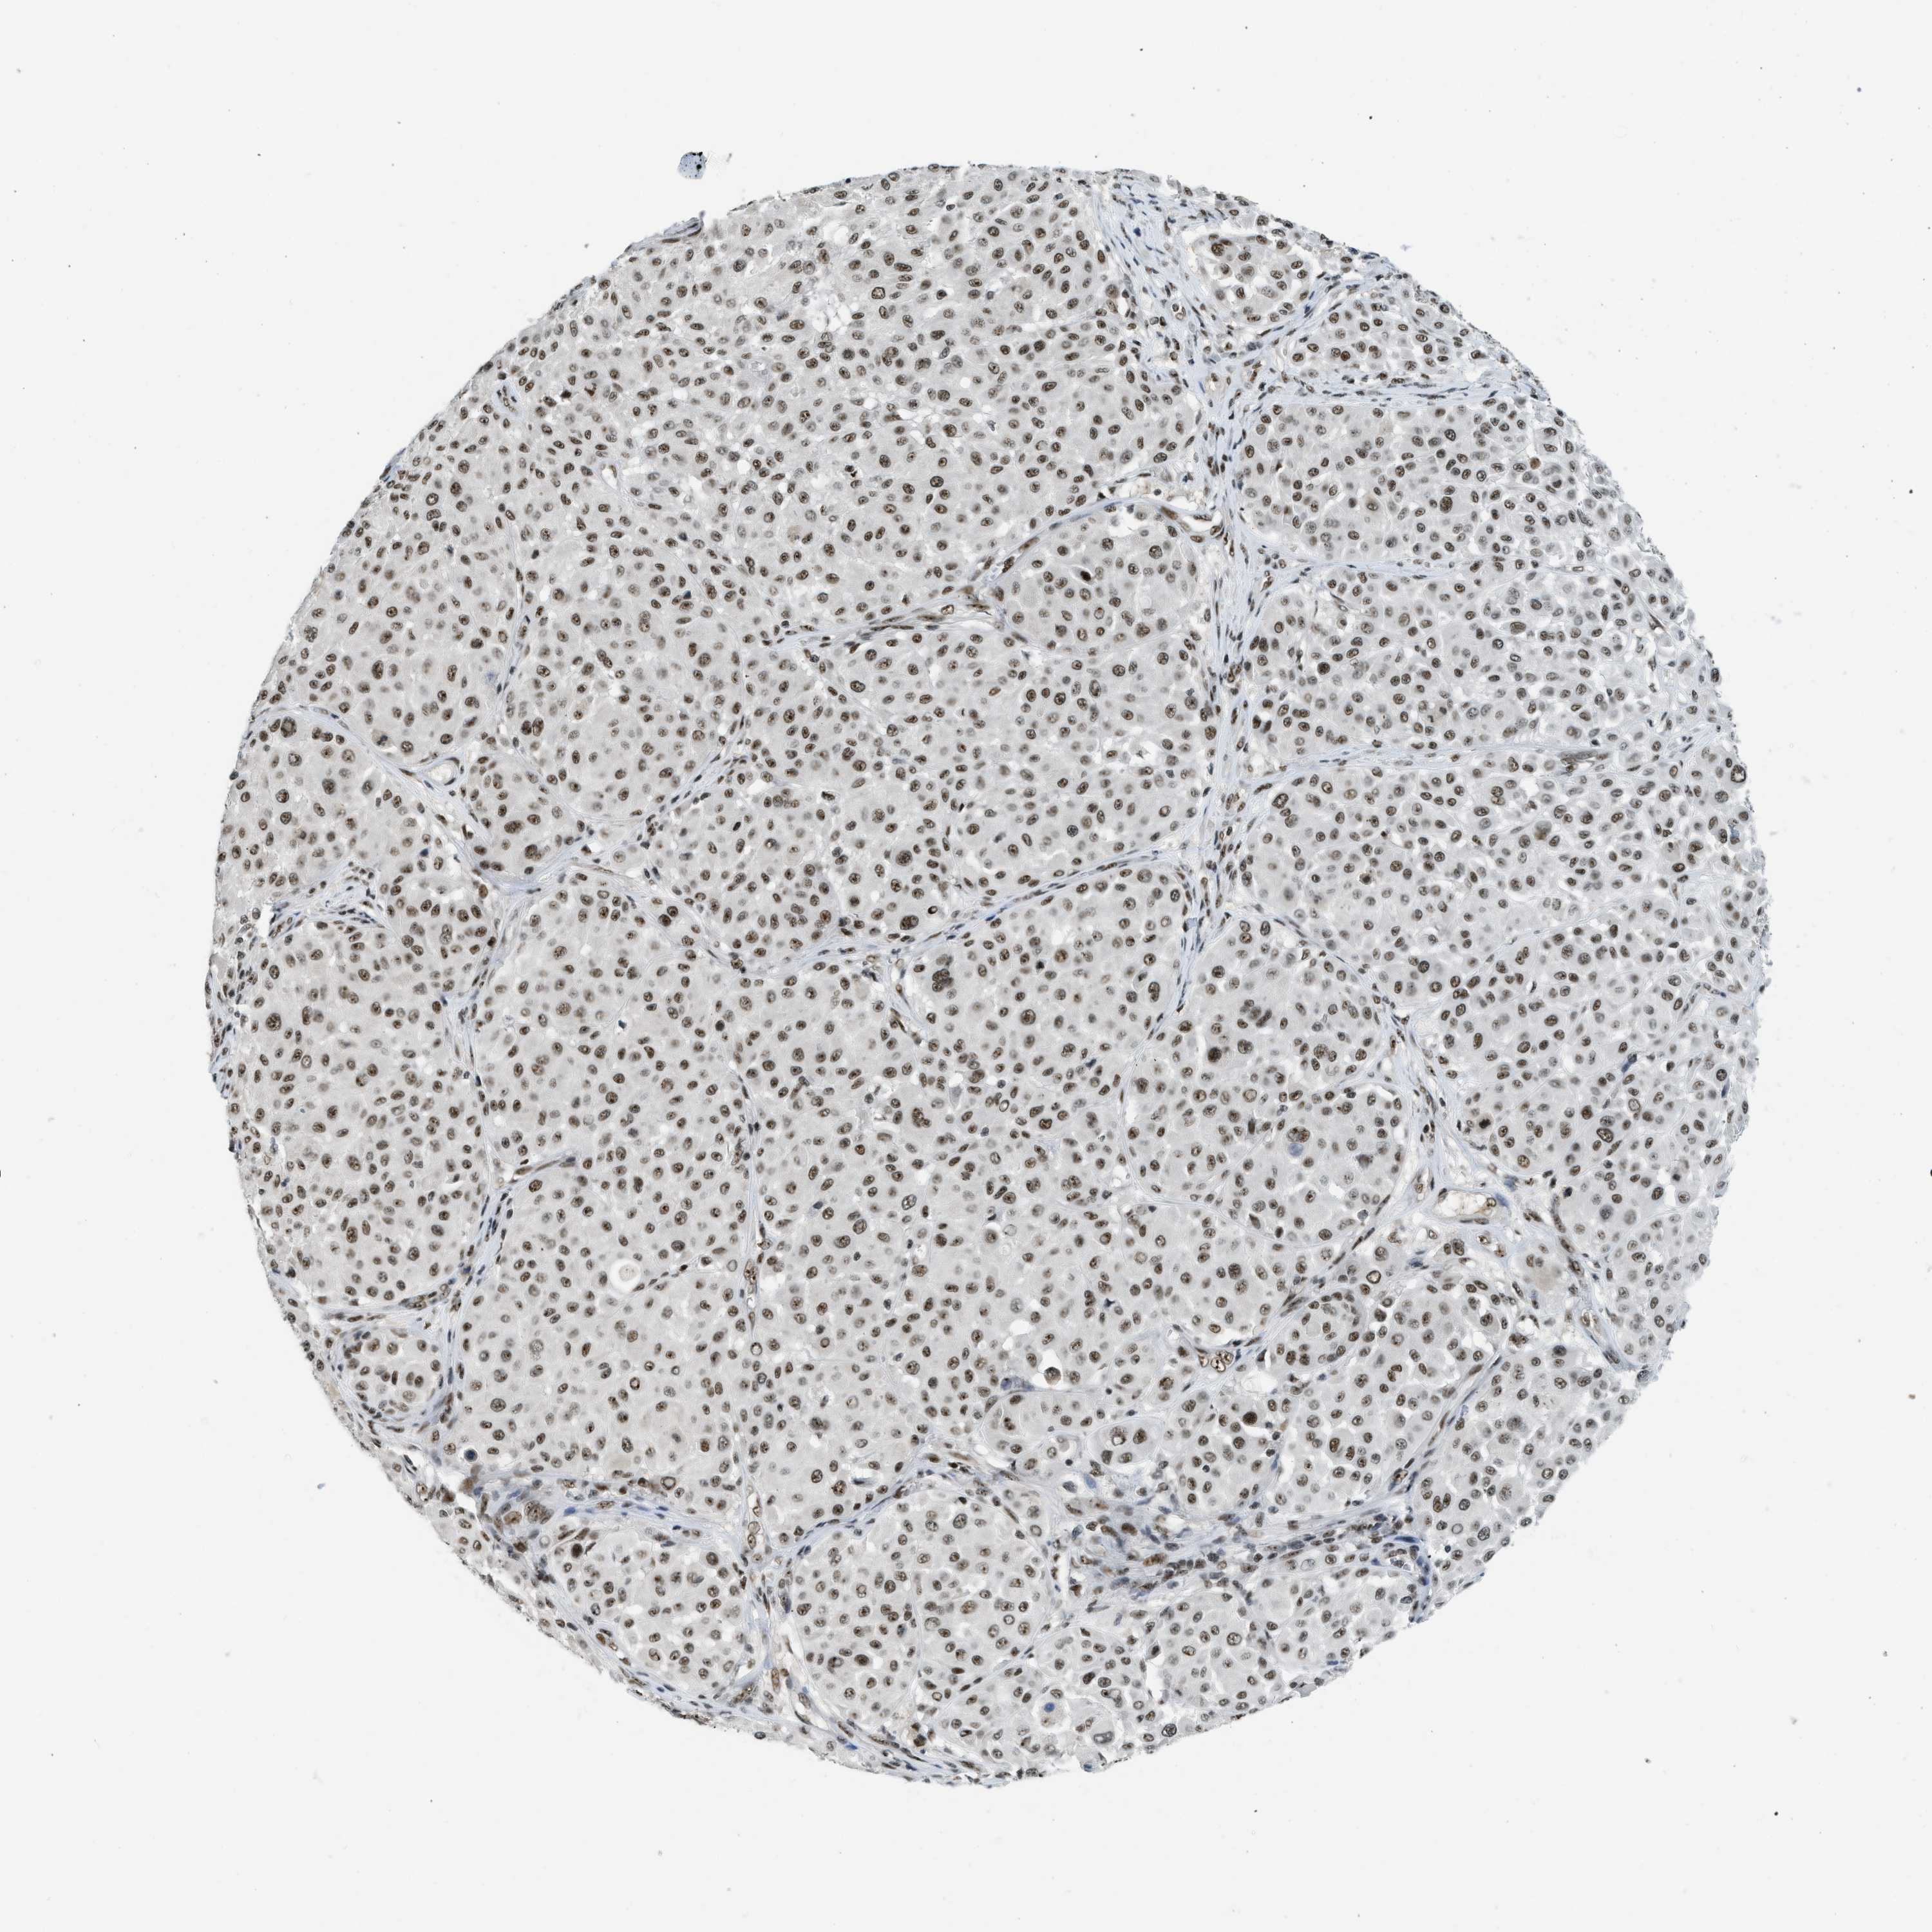

MELANOMA - Protein expressioni

A mouse-over function shows sample information and annotation data. Click on an image to view it in a full screen mode. Samples can be filtered based on level of antibody staining by selecting one or several of the following categories: high, medium, low and not detected. The assay and annotation is described here.

Note that samples used for immunohistochemistry by the Human Protein Atlas do not correspond to samples in the TCGA dataset.

Antibody stainingi

Antibody staining in the annotated cell types in the current human tissue is reported as not detected, low, medium, or high, based on conventional immunohistochemistry profiling in selected tissues. This score is based on the combination of the staining intensity and fraction of stained cells.

Each image is clickable and will lead to virtual microscopy that enables deeper exploration of all samples and also displays staining intensity scores, fraction scores and subcellular localization as well as patient and tissue information for each sample.

Antibody HPA018334

Staining

High

Medium

Low

Not detected

Intensity

Strong

Moderate

Weak

Negative

Quantity

>75%

75%-25%

<25%

None

Location

Nuclear

Cytoplasmic/membranous

Cytoplasmic/membranous,nuclear

Malignant melanoma, NOS